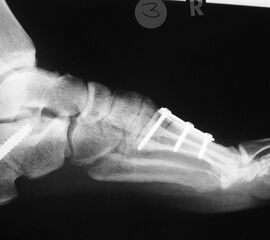

Reorientierende Chopartarthrodese nach Imhäuser/Cramer: Durch die Entnahme eines dorsalbasigen Knochenkeils unter Resektion des Chopart-Gelenks kann die direkte Hohlfußdeformität korrigiert werden. Die OP-Aufklärung sollte insbesondere wie auch bei allen anderen resezierenden Rückfußarthrodesen auf die Verkürzung des Fußes hinweisen (Abb. 36).

Reorientierende Triplearthrodese nach Hoke: Die Resektionsschnitte der Gelenklinien des subtalaren und Copartgelenkes beinhalten eine Keilform mit fußrückenseitiger Basis im Chopartgelenk. Je nach Ausmaß der Kalkaneusfehlstellung kann durch Entnahme eine Keils mit lateraler Basis im subtalaren Gelenk eine orthograde Einstellung des Rückfußes erreicht werden (Döderlein 2000).

Reorientierende Triplearthrodese nach Lambrinudi: Durch eine distalbasige Keilentnahme des Subtalargelenkes wird eine Spitzfußfehlstellung des Rückfußes in die Neutralposition überführt und somit der Dorsalflexionsanschlag im oberen Sprunggelenk therapiert (Abb. 37). Auch bei dieser Tripelarthrodese sind Korrekturen in allen drei Raumebenen möglich, in Verbindung mit einer guten Stabilisierung des Fußes, was insbesondere bei Lähmungen Vorteile bietet (Döderlein 2000).